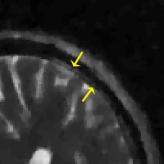

where J1subscript𝐽1J_{1} is the first kind Bessel’s function of order 111. Then using the variable density random sampling method in [46], we generate 20%percent2020\% undersampled k-space data. The complex white Gaussian noise is also added so that the resulting SNR of the samples is approximately 25dB25dB25\mathrm{dB} (See Fig. 3).

Refer to caption

(a) Fully sampled

(b) Ground truth

(c) Sample mask

(d) Undersampled

Figure 3: Dataset for the phantom experiments. Fully sampled k-space data, its inverse DFT as a ground truth, the undersampling mask, and the undersampled k-space data.